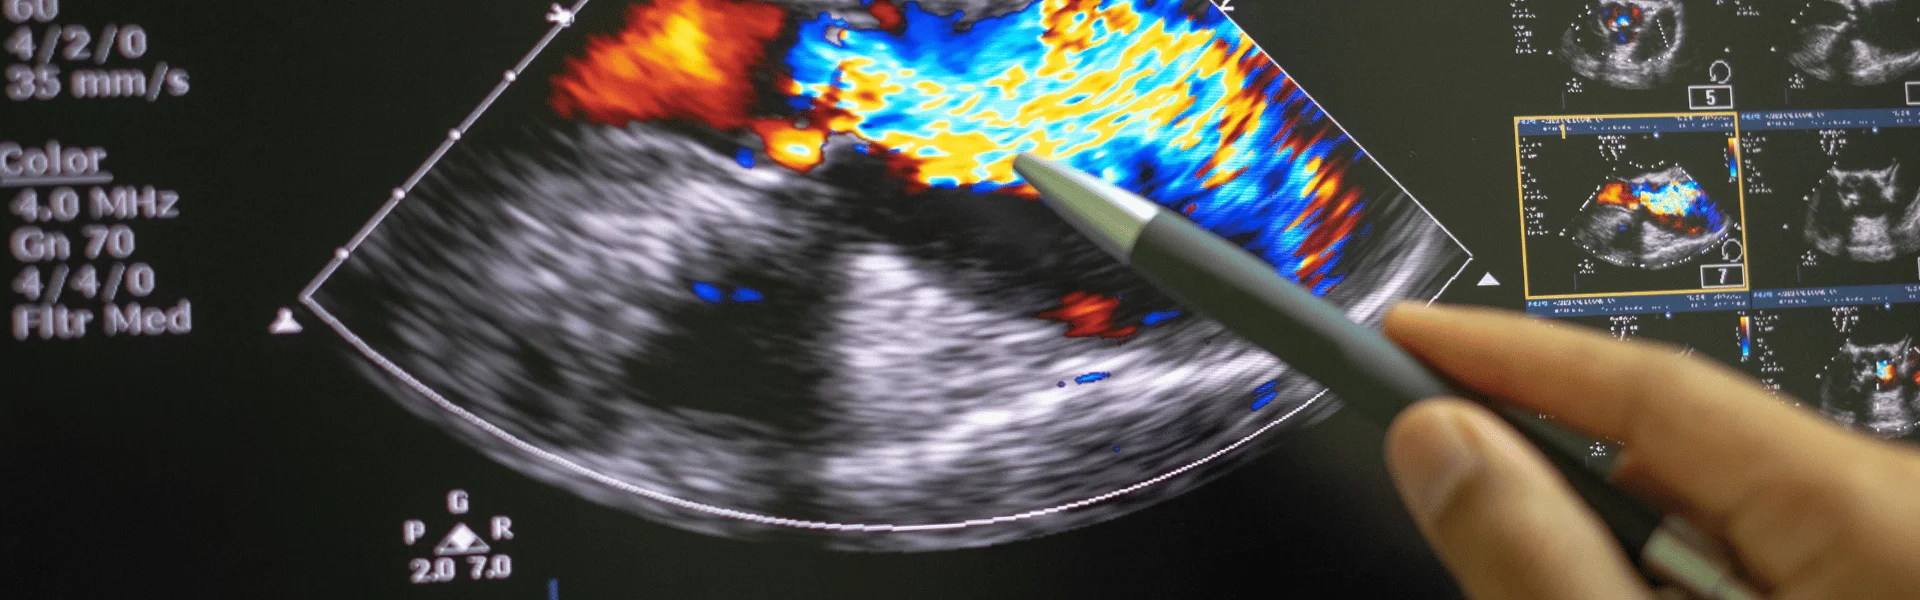

• Ultrasonido doppler: Brindamos estudios de ultrasonido doppler para evaluar el flujo sanguíneo en las arterias y venas del cuerpo.

• Ecocardiografía: Realizamos ecocardiografías para evaluar la función cardíaca y detectar posibles problemas cardíacos.